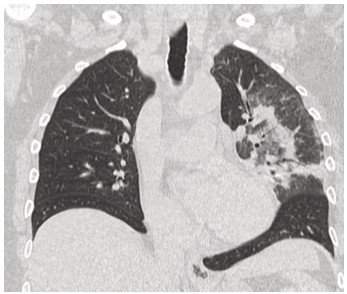

Mujer de 73 años procedente de Australia con antecedentes de hipertensión arterial, depresión, tiroiditis de Hashimoto e hipotiroidismo secundario. En las últimas semanas, como parte de su recorrido por Sudamérica, visitó Chile, Brasil, Argentina y Perú. En este último y durante su estancia en Machu Picchu, debuta con un cuadro clínico caracterizado por astenia, disnea de moderados esfuerzos, tos seca y cefalea opresiva holocraneana, tratada con medicación no especificada con mejoría parcial. Sin embargo, pocos días después y tras su llegada a Ecuador los síntomas se agudizan con aumento de la frecuencia e intensidad de la tos, así como la disnea y el compromiso general caracterizado por astenia, alza térmica y escalofrio. Tras esta presentación clínica es ingresada en el servicio de Emergencia destacando en la valoración clínica taquipnea (24 respiraciones por minuto), hipoxemia medida por pulsioximetría en 79%, con necesidad de aporte de oxígeno suplementario, taquicardia (100 latidos por minuto). En la auscultación pulmonar con presencia de crepitantes difusos y sibilancias basales, además edema de miembros inferiores. Dentro de la evaluación complementaria destaca la presencia de leucocitosis y neutrofilia, elevación de proteína C reactiva y la elevación significativa del dímero D (tabla 1). El panel respiratorio por PCR de 13 patógenos fue negativo. En los estudios de imagen infiltrados alveolares multilobares con broncograma aéreo y un estudio angiotomografico sin evidencia de defectos de llenado que sugieran tromboembolia pulmonar (TEP) (figuras 1-3).

Figura 2. Tomografía de tórax simple de alta resolución, corte coronal: presencia de consolidado con broncograma aéreo en lóbulo inferior derecho.